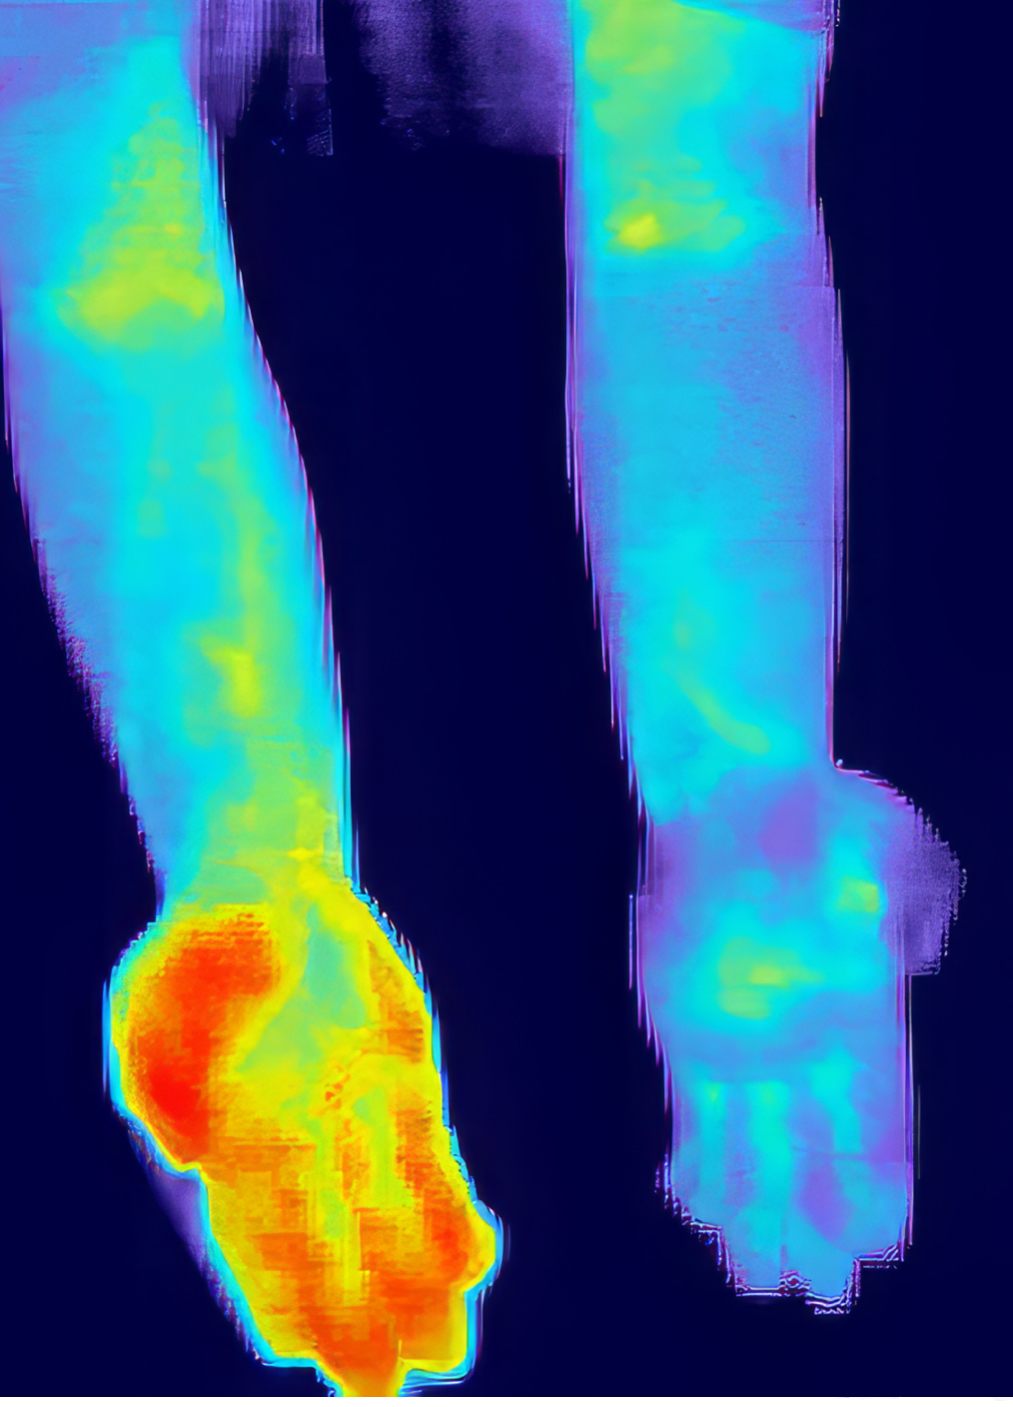

As shown in our thermal imaging examples, this technology can reveal issues that aren't apparent through traditional examination methods:

- Identifying poor circulation in non-healing wounds and ulcers

- Detecting inflammation in joints and soft tissues

- Revealing temperature asymmetries that indicate nerve or vascular issues

The MyoVision T2 system combines surface electromyography (sEMG) with thermal scanning technology to measure both muscle activity and temperature variations throughout your spine and surrounding tissues. Inflammation causes increased blood flow and temperature in affected areas, which our thermal scans can detect with precision.